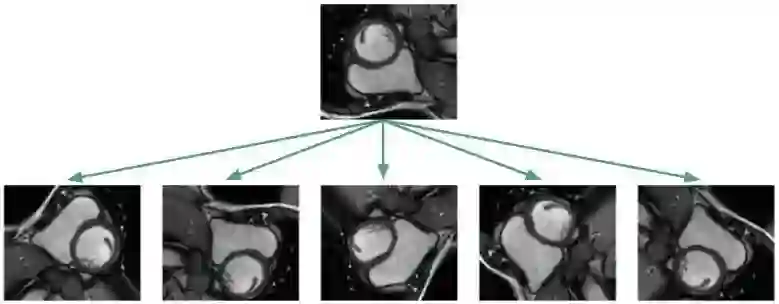

与其他数据不足的场景相同,医学图像也可以借助数据扩张实现网络的训练。比如下图所示,通过随机旋转、平移、缩放、裁剪、弹性形变等手段,对原始图像进行变换: